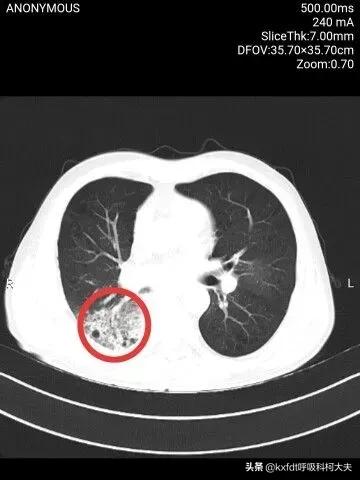

肺癌转移部位